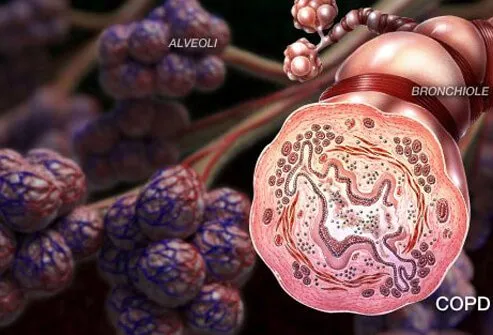

COPD可并發慢性支氣管炎或肺氣腫;一些患者會出現這兩種問題,從而導致額外的呼吸問題。一些臨床醫生認為慢性支氣管炎和肺氣腫只是 COPD的進一步表現。

許多COPD患者還會發展為慢性支氣管炎。慢性支氣管炎是一種每天都會發生的咳嗽,會導致氣道發炎、粘液過多以及頻繁的病毒或細菌感染。由于吸煙通常是慢性支氣管炎的原因,“吸煙者咳嗽”很可能是慢性阻塞性肺病和慢性支氣管炎的征兆。慢性支氣管炎的治療包括支氣管擴張劑、類固醇和氧療。還建議戒煙并避免空氣傳播的支氣管刺激物。

肺氣腫是一種肺部疾病。在肺氣腫中,肺泡(肺中促進二氧化碳和氧氣交換的小氣囊)受損并死亡。二氧化碳和氧氣沒有交換,最終肺泡死亡,在肺部留下空洞,導致肺組織丟失和 COPD 癥狀加重。肺氣腫的癥狀通常包括呼吸急促,有時還包括咳嗽和喘息。肺氣腫的治療可能包括支氣管擴張藥物、類固醇、抗生素和氧氣。強烈建議戒煙。